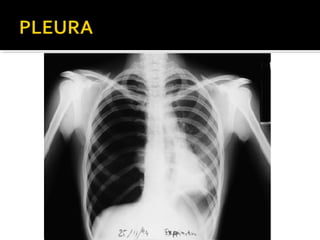

Este documento fornece parâmetros técnicos para realizar uma radiografia de tórax, incluindo posicionamento correto do paciente, dose adequada de radiação e estruturas anatômicas a serem avaliadas, como coração, pulmões, pleura, diafragma e ossos do tórax.